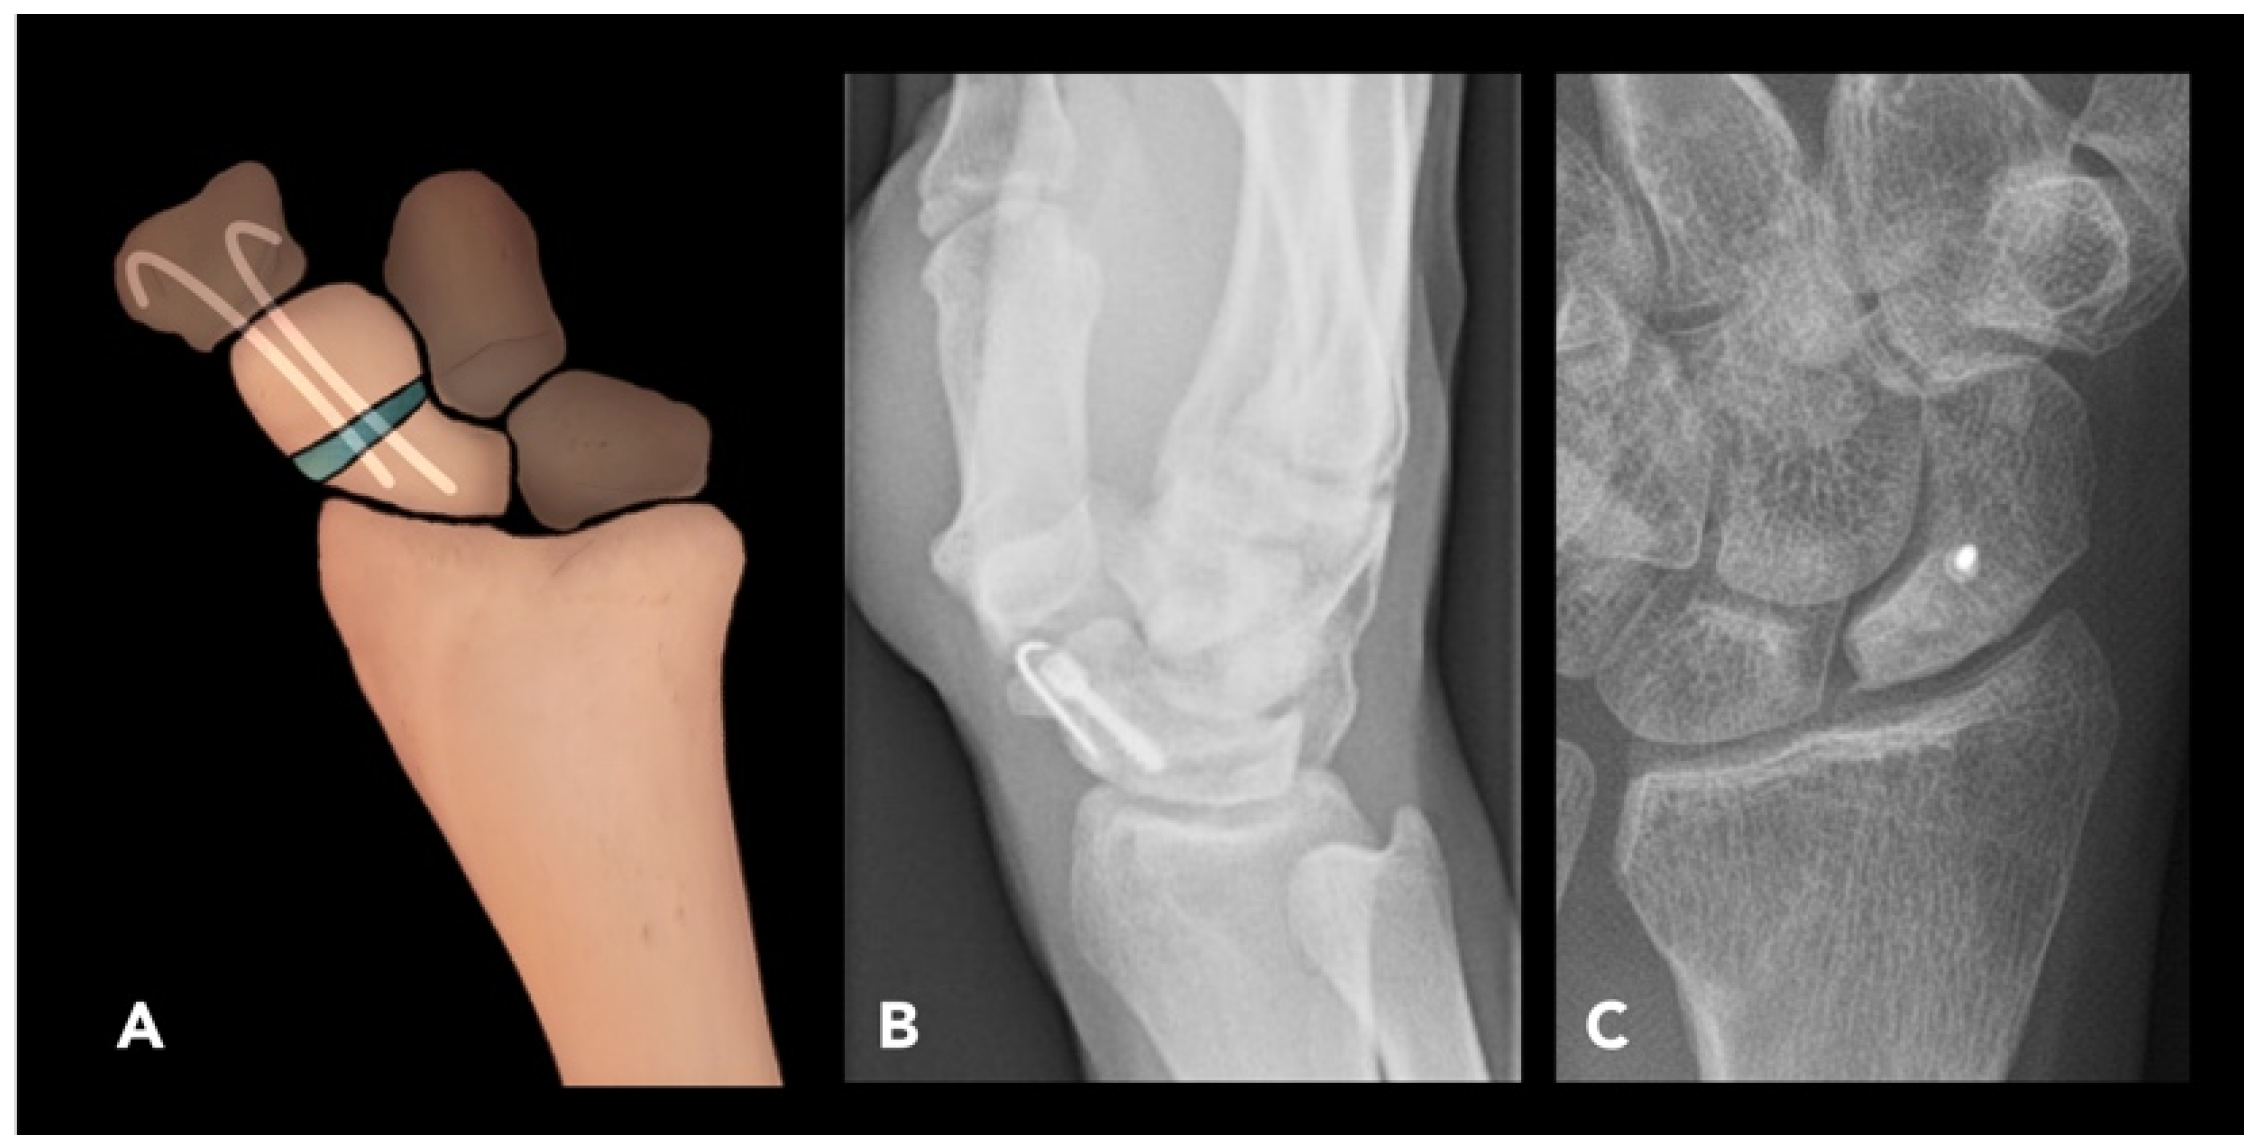

2.2.4. Scaphoid Corrective Osteotomy

2.3. Lower Extremity Osteotomies